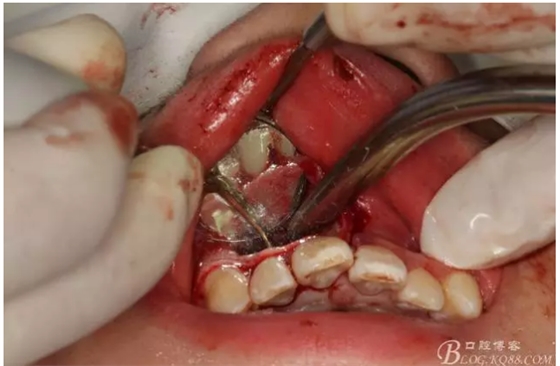

圖7.切除根尖3mm的影像

圖8.根尖區(qū)超聲倒預(yù)備3mm

圖9.去除根尖3mm牙膠。